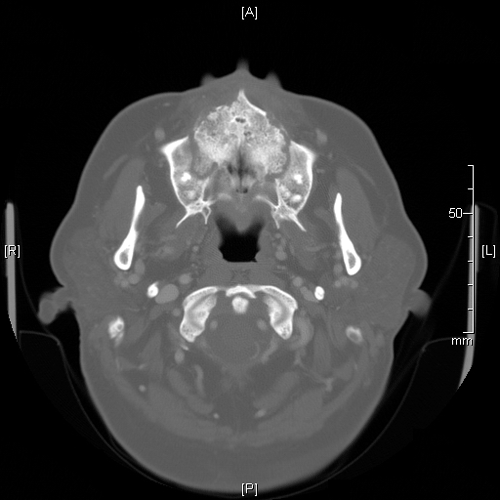

Image of the Case: CT scan, coronal view, of the sinuses reveals an opacified left ostiomeatal unit on the left and thickening of the mucosa on the right (Panel A). CT scan, axial view. The hard palate and maxilla show destructive changes and fractures causing a “moth-eaten” appearance (Panel B).

Clinical information: The patient was a 42 year-old woman with a history of acute promyelocytic leukemia status post Atra and induction chemotherapy with Idarubicin and ARA-C was admitted to the hospital for consolidation therapy. During her hospitalization she developed mucositis which gradually progressed for a few weeks. Her symptoms included sinus pain (left significantly greater than right), sinus drainage, mouth pain (particularly on the soft palate), and facial swelling. Computerized tomography (CT) scan revealed destructive changes of the hard palate and maxilla, and surgical intervention was required. Intra-operative findings included bilateral diffuse necrosis of the nasal cavities, with significant destruction of the nasal septum, left nasal turbinate, and bony nasal floor. Specimens were sent for frozen section, permanent section, and fungal cultures. The patient received antifungal therapy and required repeated sino-nasal debridement. There has been no further extension of fungal infection. Following are images from permanent section.